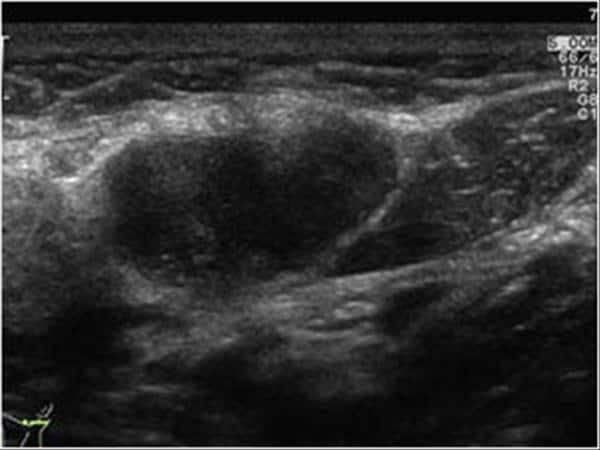

U tuyến nước bọt

» Thông tin: Nam giới – 64 tuổi.

» Lâm sàng: Khối vùng mang tai.

# U lympho tuyến nang (U Warthin) tuyến nước bọt mang tai.